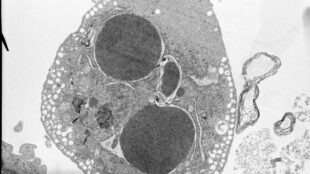

Dödliga protein-lipidkomplex styr cellens öde

Oxidativ stress i celler är en av de starkaste stimulis för att trigga programmerad celldöd. Ofta betraktas lipider och biomembran...